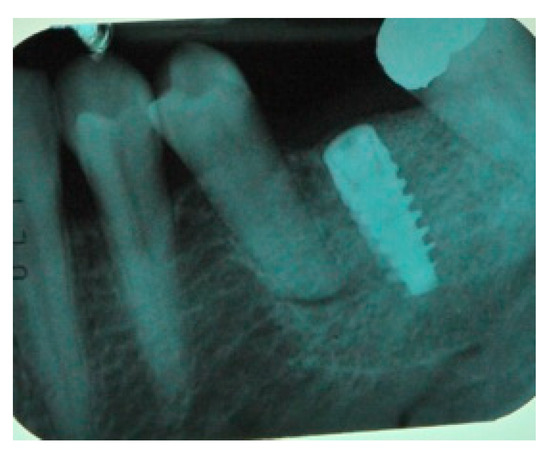

- Flap design: Soft tissue management should be as accurate as possible. The design of the flap should ensure a tension-free primary closure of the wound even after voluminous grafting of the defect. One option (preferred especially in wide vertical defects) is the execution of the so-called “poncho” flap. This technique includes a high vestibular incision of the mucosa, muscle and periosteum in order to undermine the preparation of the flap and to achieve its mobilization, followed by a deep incision in the buccal area with two additional vertical incisions that are performed at an appropriate distance from the occlusal area and the site of augmentation. After the incision, the preparation of a muco-periosteal flap and the remotion of scar tissue, a full thickness flap is raised until the bone defect is uncovered [17,18,19,20]. Finally, the positioning of the customized titanium mesh is passively tested to evaluate its fit intra-operatively (Figure 2, Figure 3, Figure 4 and Figure 5).